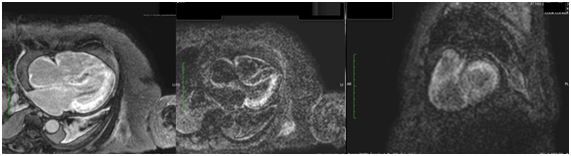

An MRI (Figure 3) was performed, reporting during inversion recoverysequences (IR) of late gadolinium enhancement the impossibility to diminish properly the left ventricle due to its global involvement and the hypo-intensity signal at intra-cavitary level, despite performing IR sequence 5 (five) minutes after contrast injections. During look Locker sequence, an impairment of more than 50% of the left ventricle myocardium was found. Leading the diagnostic suspicion of amyloidosis, a pleural puncture was performed revealing 6g/dl of protein in the exudate with a high number of lymphocytes, polymorph nuclear leucocytes, plenty of atypical mesothelial cells and a low number of atypical plasmatic cells. Bacterial and mycobacterial culture were negative.Then, a fine needle aspiration biopsy of abdominal fat was made, giving a positive result for amyloid.The patient was moved to the haemato-oncology unit in order to evaluate an alternative treatment and she died 22days later.

Figure 3 Sequence of late enhancement in short axis and in the four chambers. Impossibility to dim the myocardium properly due to global involvement, together with intracavitary hypo-intensity. Sub-endocardial and sub-epicardial diffuse involvement in left ventricle, as well as in atrial myocardium and intra-atrial septum.

Annual mortality of patients with amyloidosis and heart involvement reach yearly numbers of 24%, and in those cases where death is present in the first six months, half of them are sudden death.13,14 The grade of heart condition is a determining prognosis, and in this sense, MRI is a heavy weight prognosis attribute through determination of extracellular involvement grade.15